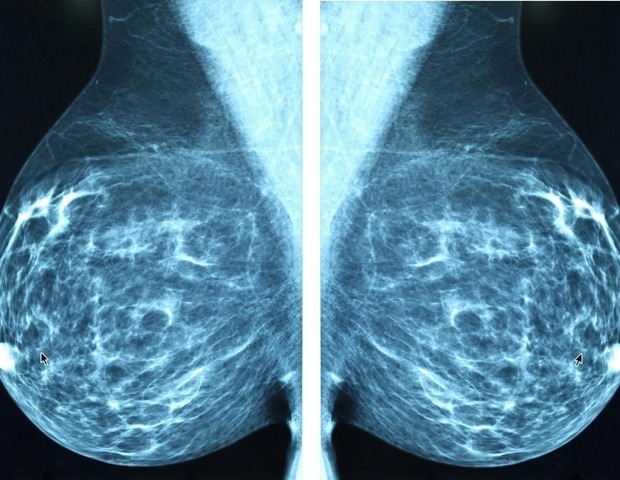

Αύξηση περιστατικών καρκίνου του μαστού σε νεότερες γυναίκες

Μια νέα μελέτη που εξετάζει δεδομένα από επτά εξωτερικές κλινικές στην περιοχή της Νέας Υόρκης, αποκάλυψε ότι το 20-24% των περιπτώσεων καρκίνου του μαστού που διαγνώστηκαν σε μια 11ετή περίοδο αφορούσαν γυναίκες ηλικίας 18 έως 49 ετών. Τα ευρήματα θα παρουσιαστούν σήμερα στη ετήσια συνάντηση της Εταιρείας Ακτινολογίας της Βόρειας Αμερικής (RSNA).

Η έρευνα δείχνει ότι ένα σημαντικό ποσοστό καρκίνων διαγιγνώσκεται σε γυναίκες κάτω των 40 ετών, για τις οποίες δεν υπάρχουν επί του παρόντος οδηγίες ανίχνευσης. Οι γιατροί που φροντίζουν γυναίκες σε αυτήν την ηλικιακή ομάδα θα πρέπει να εξετάσουν την εκτίμηση κινδύνου, προκειμένου να εντοπίσουν εκείνες που μπορεί να ωφεληθούν από πιο εντατική παρακολούθηση λόγω αυξημένου κινδύνου.

Συνολικά, διαγνώστηκαν 1,799 περιπτώσεις καρκίνου του μαστού σε 1,290 γυναίκες ηλικίας 18 έως 49 ετών, με τη μέση ηλικία διάγνωσης να είναι 42,6 χρόνια. Οι ετήσιες διαγνώσεις κυμάνθηκαν από 145 έως 196, με το 41% των περιπτώσεων να ανιχνεύεται μέσω προληπτικών εξετάσεων και το 59% μέσω διαγνωστικών αξιολογήσεων. Από αυτές, οι 1,451 περιπτώσεις (80,7%) ήταν επεμβατικοί καρκίνοι, ενώ οι 347 (19,3%) ήταν μη επεμβατικοί.

«Οι περισσότερες από αυτές τις περιπτώσεις ήταν επεμβατικές, γεγονός που σημαίνει ότι μπορούν να εξαπλωθούν πέρα από τον μαστό, και πολλές ήταν επιθετικοί τύποι, ειδικά σε γυναίκες κάτω των 40», δήλωσε η Δρ. Δεστούνις. «Ορισμένες περιπτώσεις ήταν ‘τριπλά αρνητικές’, μια μορφή καρκίνου του μαστού που είναι πιο δύσκολο να αντιμετωπιστεί, καθώς δεν ανταποκρίνεται σε κοινές ορμονικές θεραπείες».

Αξιοσημείωτο είναι ότι, παρά το γεγονός ότι οι γυναίκες κάτω των 50 ετών αποτελούσαν το 21% έως 25% των ετησίως εξεταζόμενων, αντιπροσώπευαν σταθερά το ένα τέταρτο των διαγνώσεων καρκίνου του μαστού. «Αυτό είναι εντυπωσιακό, καθώς δείχνει ότι οι νεότερες γυναίκες όχι μόνο φέρουν ένα σταθερό και σημαντικό ποσοστό του βάρους του καρκίνου του μαστού, αλλά οι όγκοι τους είναι συχνά βιολογικά επιθετικοί», πρόσθεσε η Δρ. Δεστούνις.